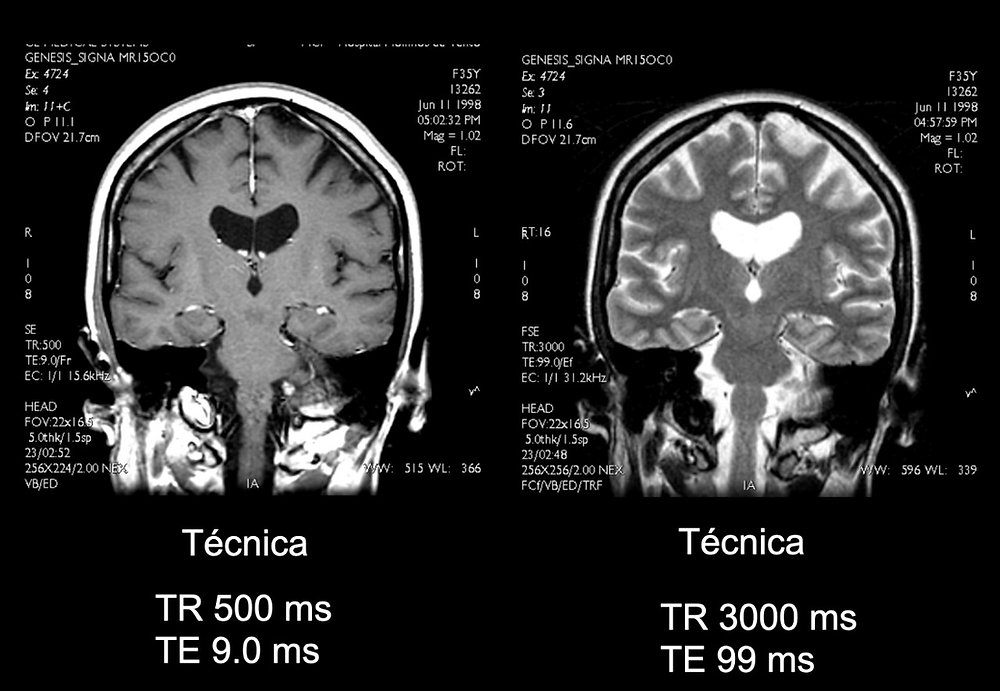

Em RM:

- Fast Brain (avaliar hidrocefalia, lesões focais)